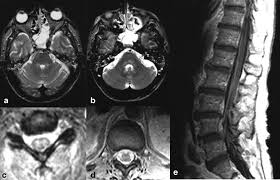

Watershed distribution ischemia in areas remote from the primary herpetic lesions may be seen. Herpes simplex encephalitis typically manifests in older adults (about 50% of cases) with headache, fever, altered sensorium, and even seizure. Hippocampus, temporal lobe, and the ponsfigure 4a.7. Herpes simplex virus (hsv) is the most common cause of acute fatal sporadic encephalitis, with a particular predilection for the limbic system. Unfortunately, the imaging findings are often nonspecific with overlapping appearances. This lesion was seen in all patients as the disease progressed. Severe edema, petechial hemorrhage, and massive hemorrhagic tissue necrosis can be seen on gross specimens. He was managed with intravenous acyclovir 30mg/kg and supportive therapy. that appeared in a recent issue of clinical infectious diseases. However, mimics of hse, including other infections and increasingly recognized autoimmune causes, have been described in cases of tl encephalitis. But changes are not specific for hsv (e.g. The characteristic feature of hse is hemorrhagic necrosis of the temporal lobe. The basal ganglia are usually spared.

Herpes simplex (hsv) encephalitis is the most common cause of fatal sporadic fulminant necrotizing viral encephalitis and has characteristic imaging findings. Metabolic, vascular, neoplastic, infective and paraneoplastic diseases. A 40‑year‑old male patient with herpes simplex virus encephalitis presented with altered sensorium. Key imaging features include bilateral or unilateral signal abnormality in the temporal lobes that extends to the limbic system, early hemorrhagic changes, restriction on dwi, and abnormal enhancement. Mri revealed hyperintensities on t2 weighted images in both frontal and temporal lobes suggestive of herpes simplex encephalitis (fig 1).

A feasibility study of quantifying longitudinal brain changes in herpes simplex virus (hsv) encephalitis using magnetic resonance imaging (mri) and stereology. In the present study, flair bth was most frequently seen in patients with hsv encephalitis. Mri is the diagnostic modality of choice abnormal in 90%; Herpes simplex virus (hsv) encephalitis hsv encephalitis (hsve) is the most common cause of infectious encephalitis (1); The basal ganglia are usually spared. Encephalitis, magnetic resonance imaging, meningoencephalitis, viral. that appeared in a recent issue of clinical infectious diseases. Although far less common, essentially any part of the central nervous system can be involved 9. 1 mri t2 weighted image, showing bilateral temporal lobe hyperintensities. However, mimics of hse, including other infections and increasingly recognized autoimmune causes, have been described in cases of tl encephalitis. Two subtypes are recognized which differ in demographics, virus, and pattern of involvement. Because early diagnosis is possible in more cases of herpes simplex encephalitis (hse) as a result of the high sensitivity of mri, now widely available, a larger number of patients are receiving appropriate treatment with iv acyclovir. Limbic encephalitis, mca ischaemia, tumours, effects of seizures) hyperintense t2 signal in the medial temporal lobes, inferior frontal lobes and insula basal ganglia are usually spared